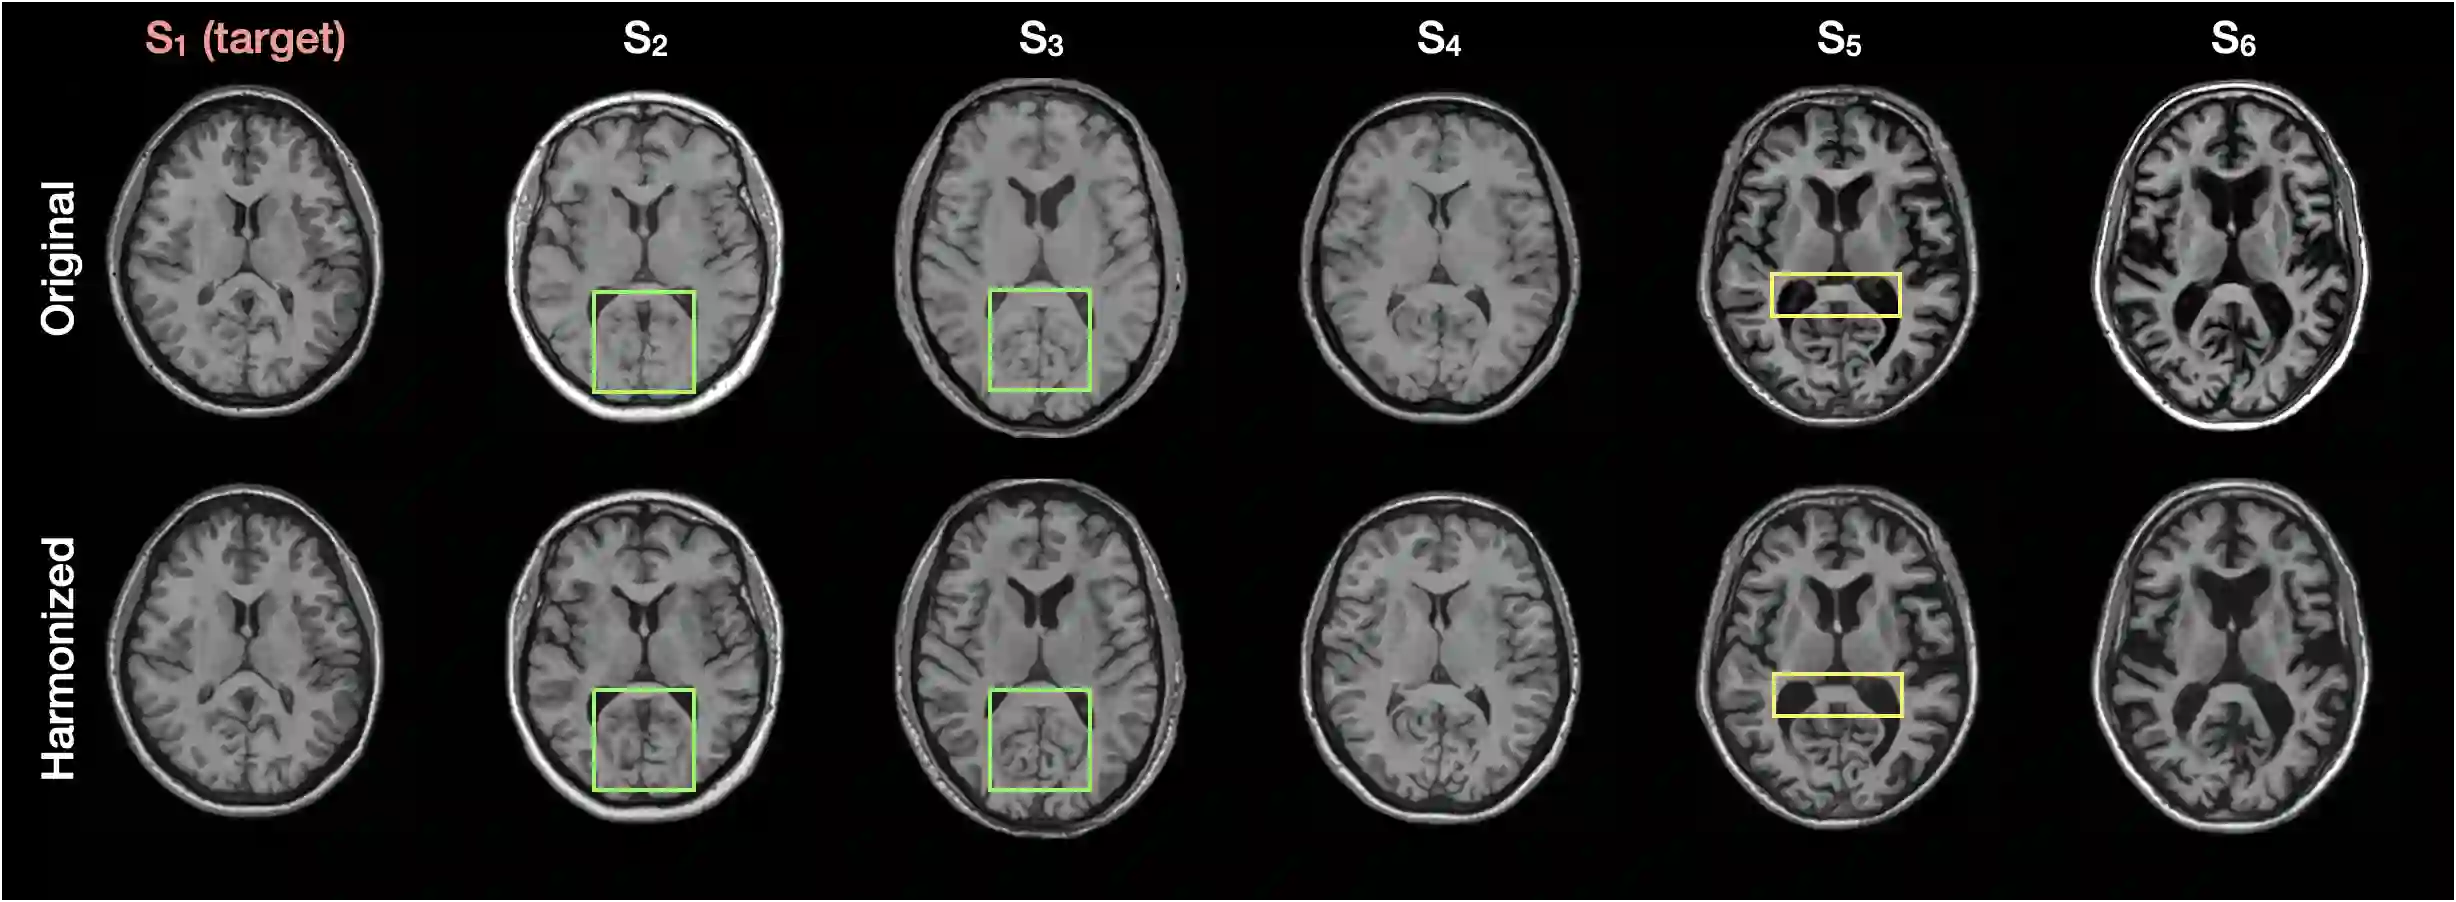

Disentangling anatomical and contrast information from medical images has gained attention recently, demonstrating benefits for various image analysis tasks. Current methods learn disentangled representations using either paired multi-modal images with the same underlying anatomy or auxiliary labels (e.g., manual delineations) to provide inductive bias for disentanglement. However, these requirements could significantly increase the time and cost in data collection and limit the applicability of these methods when such data are not available. Moreover, these methods generally do not guarantee disentanglement. In this paper, we present a novel framework that learns theoretically and practically superior disentanglement from single modality magnetic resonance images. Moreover, we propose a new information-based metric to quantitatively evaluate disentanglement. Comparisons over existing disentangling methods demonstrate that the proposed method achieves superior performance in both disentanglement and cross-domain image-to-image translation tasks.